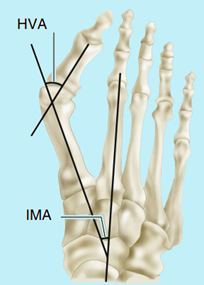

▶拇外翻测量最重要的三个角:

▶▶正常:拇外翻角HVA <20°,第1、2跖间角IMA<9°,跖骨远端固定角 DMAA <7.5°

▶▶轻度:20度< HVA <30度之间;11度< IMA<13度之间

▶▶中度:30度

▶▶重度:HVA>40度以上;IMA>16度以上

以上数据只要达到一项,即可定位该类型。

图3:拇外翻角(HVA)和第1、2跖间角(IMA)的测量

图4:跖骨远端固定角(DMAA)的测量,青少年拇外翻常伴有DMAA增大